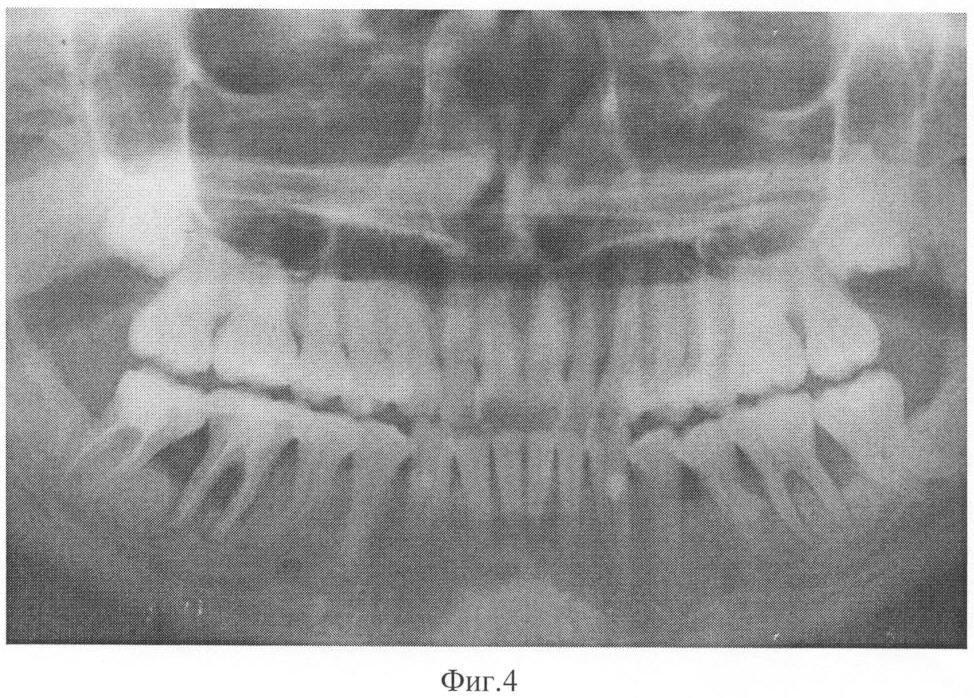

На фиг.4 – рентгенограмма пациента 2 после лечения заявленным способом.

Данные лабораторных исследований. ПТГ=34,4 пг/мл, кальцитонин 3,9 нг/л, кальций общий 2,48 ммоль/л, кальций ионизированный 1,1 ммоль/л. Сама пациентка отмечает значительное улучшение состояния, исчезновение кровоточивости десен и подвижности зубов, отсутствие рецидивов заболевания более 3 лет. Пример подтверждается рентгенограммами, выполненными до лечения – фиг.3 и после лечения – фиг.4.